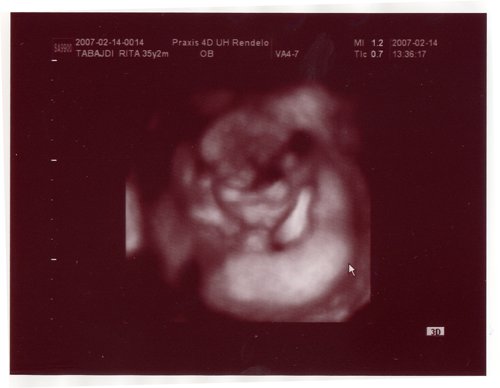

no itt van a babuci..kicsit homályos..

kissé felülnézetből..a jobb oldalán az a vastagabb rész a méhlepény..

a baba keze a szája előtt van, a másik pedig a fejénél..

kismanós forma

kismanós forma, remélem azért valamennyire látjátok